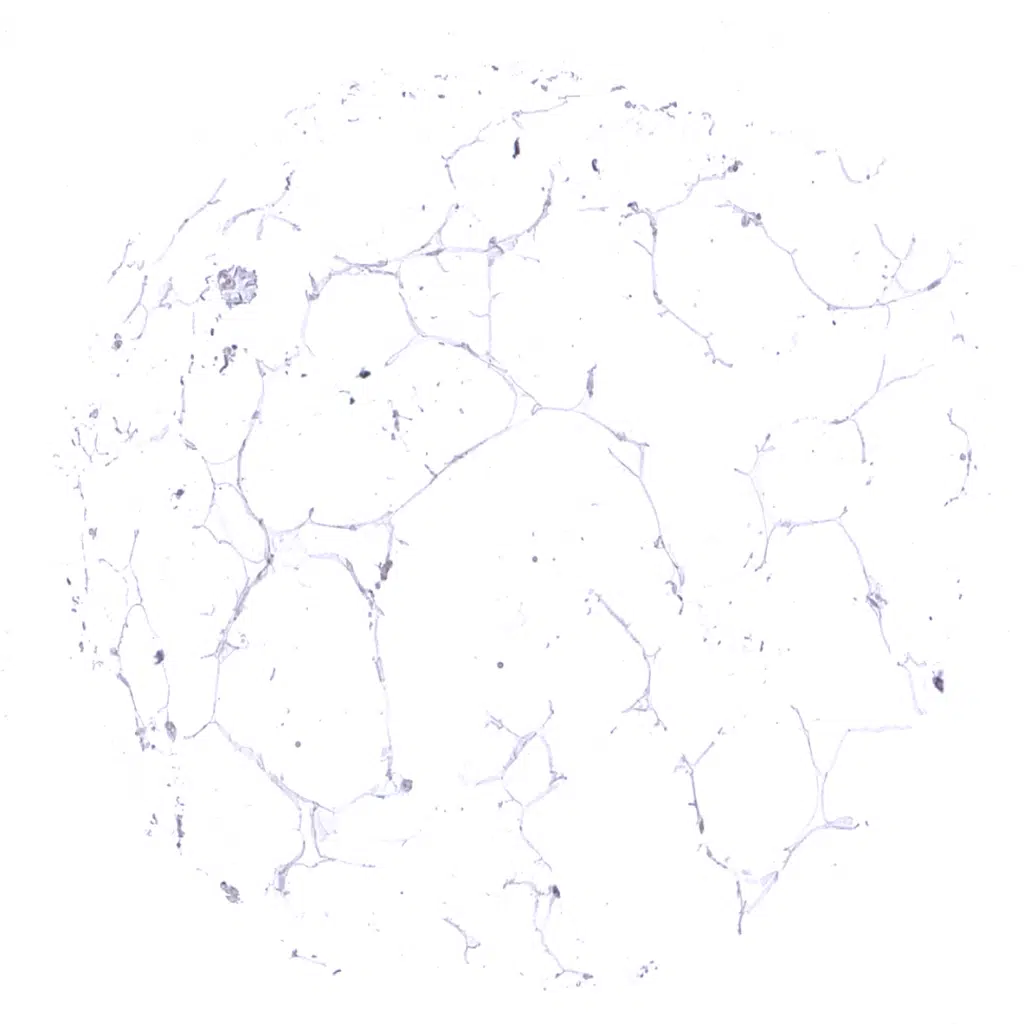

Fat